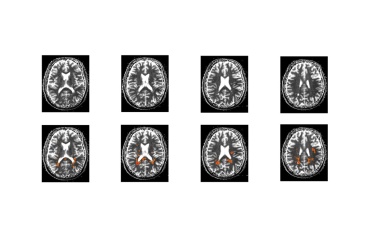

2024 hat Siemens Healthineers einen Biomarker zur Risikobewertung bei schubförmiger Multipler Sklerose (RMS) auf den Markt gebracht.

Die Messung des Myelinwasseranteils in Kombination mit biophysikalischer Modellierung stellt einen entscheidenden Fortschritt in der MS-Diagnostik dar.